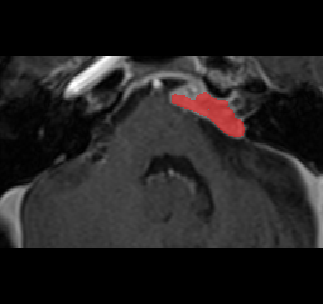

Recently, deep learning methods have achieved state-of-the-art performance in many medical image segmentation tasks. Many of these are based on convolutional neural networks (CNNs). For such methods, the encoder is the key part for global and local information extraction from input images; the extracted features are then passed to the decoder for predicting the segmentations. In contrast, several recent works show a superior performance with the use of transformers, which can better model long-range spatial dependencies and capture low-level details. However, transformer as sole encoder underperforms for some tasks where it cannot efficiently replace the convolution based encoder. In this paper, we propose a model with double encoders for 3D biomedical image segmentation. Our model is a U-shaped CNN augmented with an independent transformer encoder. We fuse the information from the convolutional encoder and the transformer, and pass it to the decoder to obtain the results. We evaluate our methods on three public datasets from three different challenges: BTCV, MoDA and Decathlon. Compared to the state-of-the-art models with and without transformers on each task, our proposed method obtains higher Dice scores across the board.